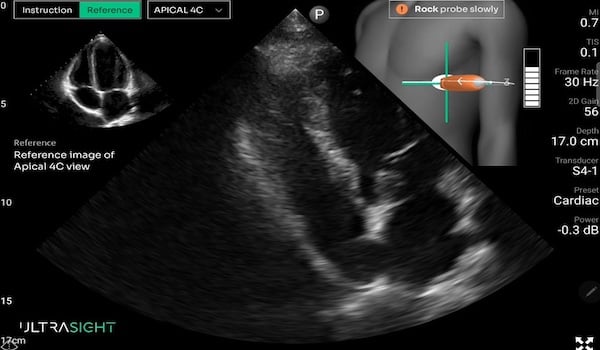

UltraSight’s AI-driven software allows health-care professionals to consistently perform high-quality ultrasound in a variety of settings, including the emergency department and intensive care unit. Photo: UltraSight

Artificial intelligence (AI) brings the promise of expediting cardiac triage by allowing clinicians to perform cardiac ultrasounds at the bedside without sacrificing image quality. One such technology is the Echo Stewardship Platform from UltraSight. It combines real-time AI guidance and a built-in image-quality meter with structured training for non-sonographers.

UltraSight is compatible with most ultrasound devices. The platform processes and stores data inside a health system’s local environment rather than sending it to the cloud, keeping protected health information (PHI) secure. AI within the platform provides users with visual and directional cues. An on-screen meter offers insight into whether images are diagnostic quality.